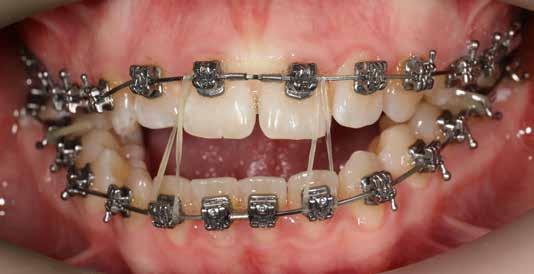

A Pitts21-es fix készülékes kezelés során a harapásemelőket a felső nagyőrlő fogakra ragasztottuk, hogy a felső molárisok intrúziójával segítsék a harapás zárását (8. kép) Ún. keresztharapásos, majd később normál class 2-es gumihúzással (9–10. képek), továbbá az elülső fogakon alkalmazott ún. Rainbow harapás-záró gumihúzással (11. kép) korrigáltuk a jobb oldali teljes premolárisnyi distal-harapást, valamint az elülső nyitott harapást.

6 hónap után a nyitott harapás már nagyjából összezárásra került (12. kép)! A gumihordás a kezelés teljes hosszában folyamatos, éjjel-nappal, 22-24 órában az étkezések és az utánuk történő fogmosás kivételével.